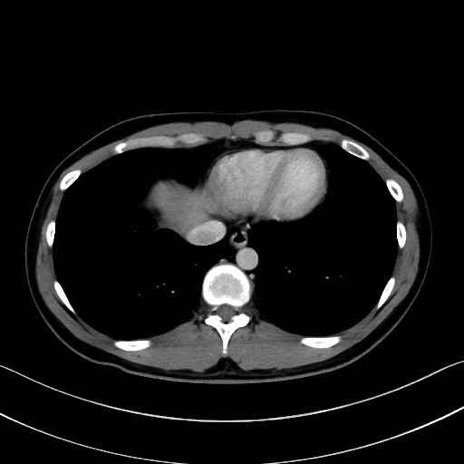

広背筋 (Latissimus dorsi)

脊柱起立筋 (Erector spinae)

多裂筋 (Multifidus)